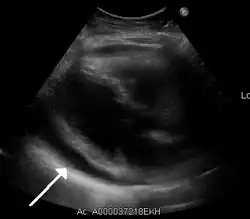

The diagnosis of tamponade can be confirmed with trans-thoracic echocardiography (TTE), which should show a large pericardial effusion and diastolic collapse of the right ventricle and right atrium. Chest X-ray usually shows an enlarged cardiac silhouette ("water bottle" appearance) and clear lungs. Pulmonary congestion is typically not seen because equalization of diastolic pressures constrains the pulmonary capillary wedge pressure to the intra-pericardial pressure (and all other diastolic pressures).